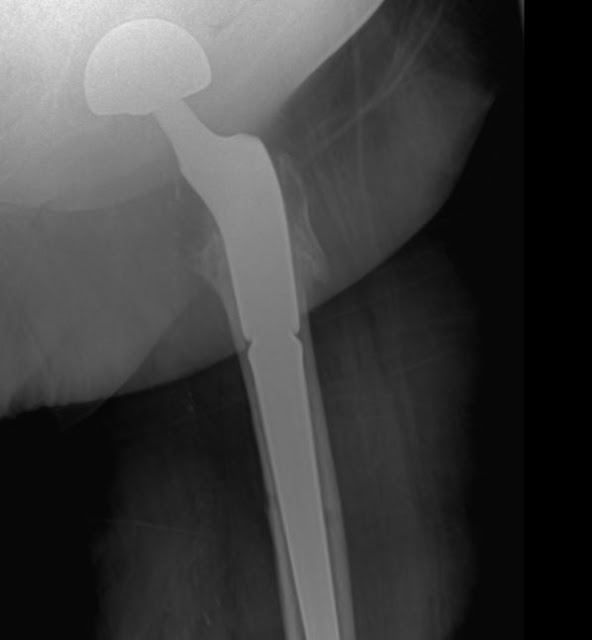

The Arcos Modular Femoral Revision System has the ability to use auxiliary implants to reattach the trochanteric fragment directly to the implant The Arcos System's three proximal and five distal geometry options provide surgeons

Zimmer Biomet's Arcos Modular Femoral Revision System meets the demands of complex hip revision surgery by offering surgeons and OR staff the ability to customize both the hip implant and its corresponding instruments Three proximal and five distal geometry options provide surgeons 117 proximal/distal combinations and multiple auxiliary. Contact a supplier or the parent company directly to get a quote or to find out a price or your closest point of sale.

Arcos Modular Femoral Revision System Hip Replacement Implant. With its broad range of femoral, acetabular, and auxiliary options, it caters to a diverse array of bone conditions, empowering surgeons to adopt a more personalised, patient-specific approach. 2,308 views February 07, 2022 Posted in HipsCenter, Zimmer Biomet Hip.